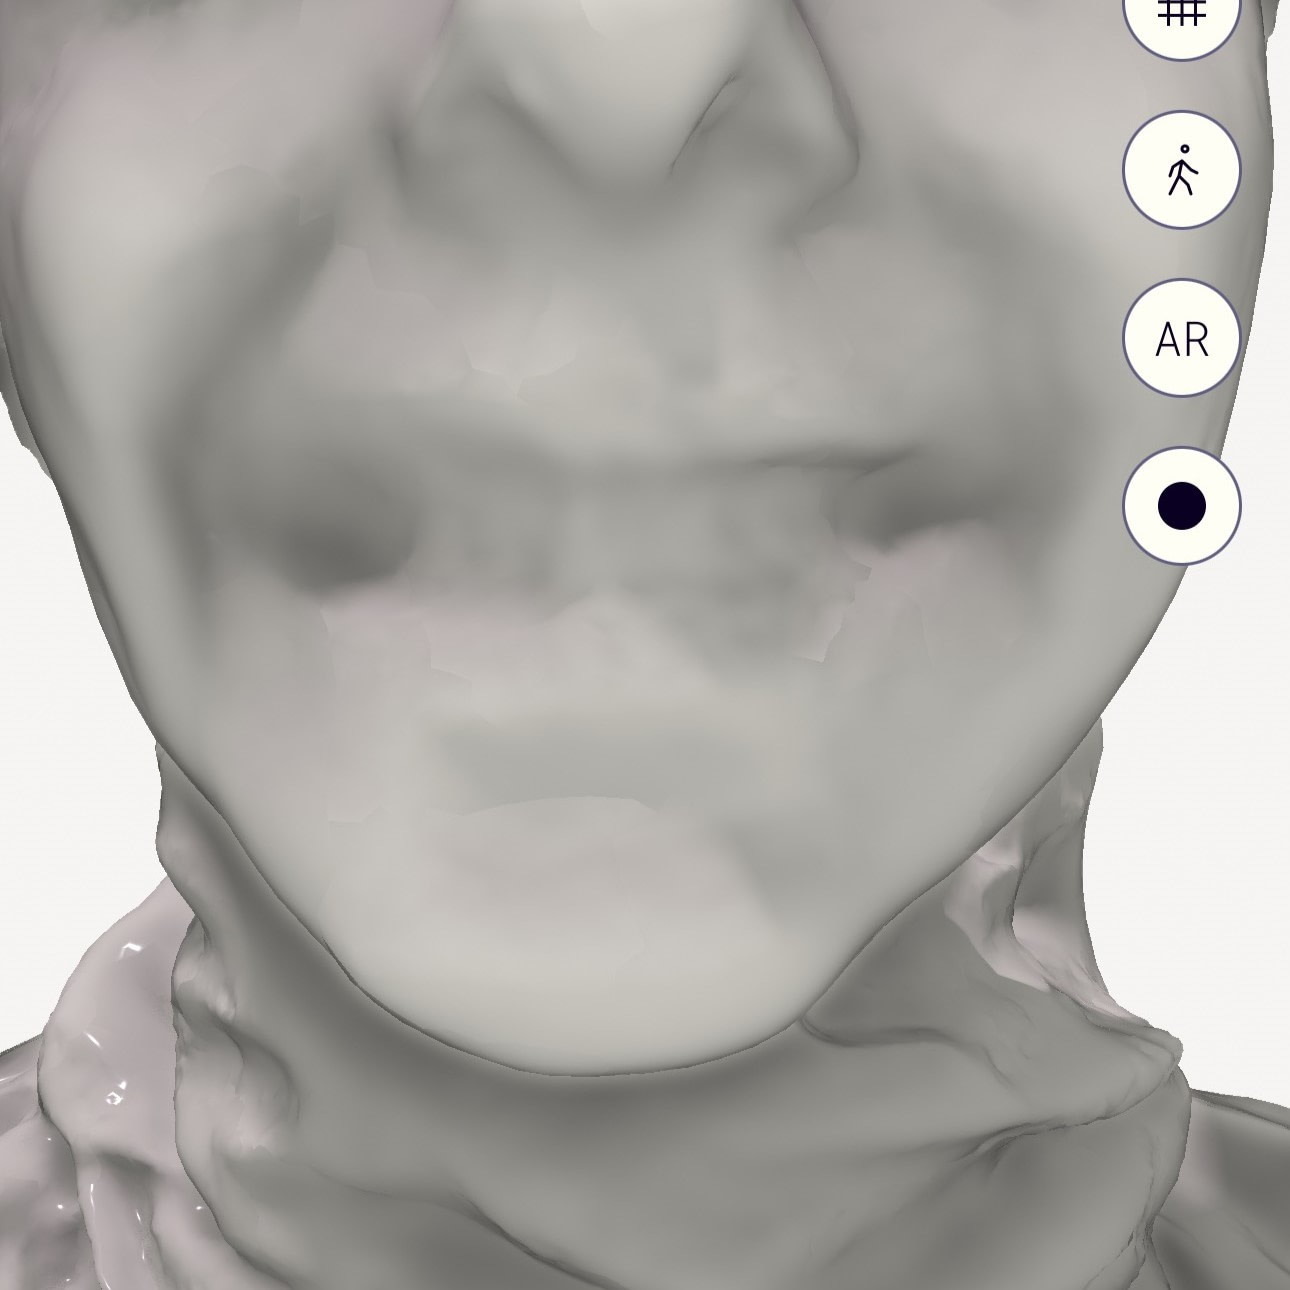

Also note the distortion in the face scanning with iPhone apps. It is interesting to see how the edges of the teeth are not exactly perfect. How much does this impact the alignment of IOS? Let's check without colour.

RayFace

Original Qlone

MetiSmile

Qlone Dental Pro

A few things stick out straight away. Obviously the dental specific scanners like RayFace and Metismile do the best. Very good details especially by RayFace but MetiSmile also did well and is one quarter of the cost.

The iPhone apps don't do as well and don't seem to have the resolution. With the original Qlone app you can see the downfall of this and many iPhone apps that are used to take a face scan. Although they can make the colour image look good, when you turn off the colour, you can clearly see the issues. How do you align an intraoral scan to this confidently?

In saying that, the new Qlone Dental Pro is a big improvement no doubt. So these are not just marketing claims. The new app really does capture the teeth and lips to a higher detail - but this cannot be thanks to hardware as I am using the same phone - it must be just smarter algorithms.

Although with the new app there is much more detail to be seen, the question is - does this look like the patient's actual teeth?